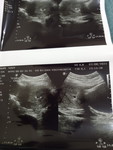

USG kehamilan tidak sesuai HPHT

Mohon pencerahan semuanya..kalau berdasarkan HPHT, usia kehamilan saya adalah 7 minggu. namun saat USG terlihat kantung kehamilan saja dan dokter menyatakan usianya 5 minggu. apakah ada yang serupa? ini kehamilan kedua setelah anak pertama usia 9 tahun..apakah normal ya 5 minggu hanya kelihatan kantung saja?mohon infonya yaa..